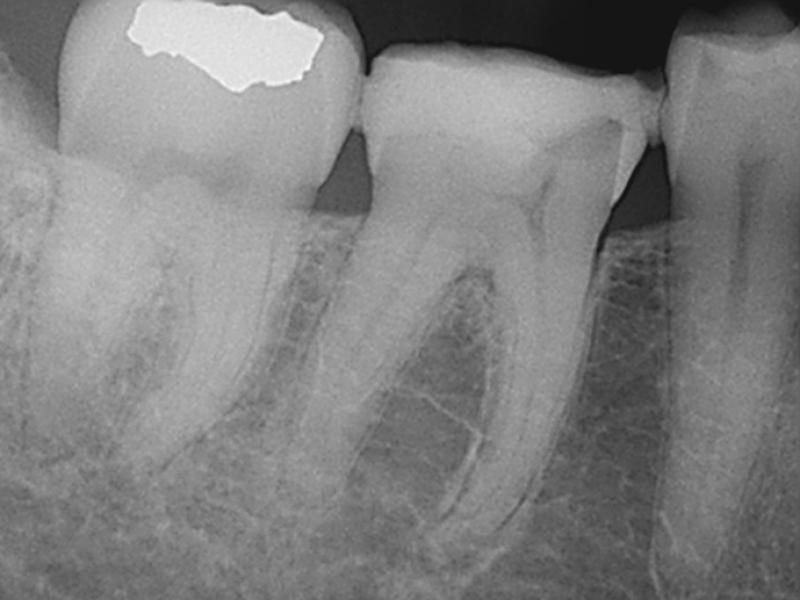

Pre-Op